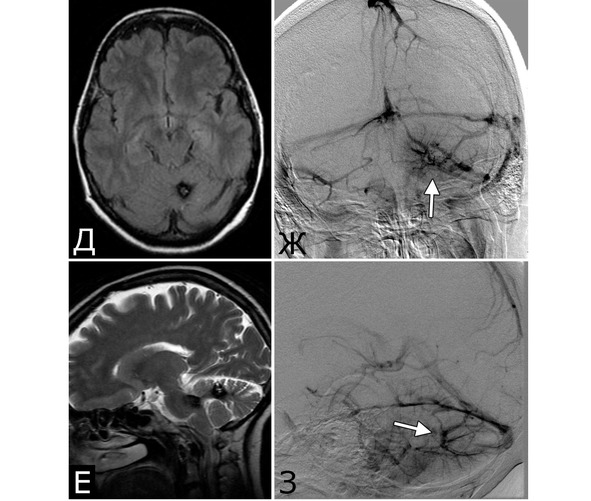

Рис. 1. Б-ная Г., 27 лет. Сочетанная сосудистая патология мозга: КМ передне-медиальных отделов височной доли справа (А – МРТ, режим Т1; Б – МРТ, режим Т2); АВМ медиальных отделов лобно-теменной области справа (В – МРТ, режим Т2; Г – МРТ-АГ). Клиническое течение: редкие вторично-генерализованные судорожные эпилептические припадки, начинающиеся с судорог в левых конечностях

Рис. 2. Б-ной П, 22 г. Сочетанная сосудистая патология мозга: Множественные КМ головного мозга. Аномалия развития венозной системы мозга. А – КМ височной, теменной и затылочной долей слева (МРТ, режим Т2, аксиальная проекция). Б, В – аномалия развития костей и оболочек мозга в виде локальной деформации внутренней костной пластинки и губчатого вещества теменных костей в области впадения патологической вены в ВСС. Расщепление аномального ВСС на две лакуны, пролабирование мозга в область дефекта (МРТ, режим Т1, сагиттальная и фронтальная проекции). Г – аномалия венозной системы в виде отсутствия прямого синуса, формирования крупной патологической вены, впадающей в заднюю треть ВСС (МРТ-АГ, сагиттальная проекция)

Рис. 3. Б-ной К-ов, 37 лет. Сочетанная сосудистая патология мозга: КМ глубинных отделов лобной доли слева (А – МРТ, режим Т2); две аневризмы ВСА справа (Б, В – СКТ-АГ, аневризмы указаны стрелками). Течение болезни: за 6 месяцев до поступления перенес два генерализованных судорожных припадка. При МРТ выявлена КМ лобной доли слева, которая послужила причиной припадков. При СКТ-АГ выявлены две аневризмы ВСА справа (случайная находка). Лечение: 1-ая операция – клипирование двух аневризм ВСА справа. 2-ая операция – удаление каверномы левой лобной доли

1. Опухоль (менингиома) мосто-мозжечкового угла справа (А – МРТ с введением КВ, режим Т1, аксиальная проекция, Б – МРТ, режим Т2, сагиттальная проекция); 2. КМ верхнее-медиальных отделов левой гемисферы мозжечка (В, Д – МРТ, режим Т1, аксиальная проекция, Г, Е – МРТ, режим Т2, сагиттальная проекция. Стрелкой указана дополнительная тень гиперинтенсивного сигнала – косвенный признак венозной ангиомы). 3. Венозная ангиома (стрелки) левой гемисферы мозжечка (Ж, З – прямая АГ, венозная фаза). Клиническое течение: в течение нескольких лет – сильные стреляющие и ноющие боли в левой половине лица и головы

Представляет интерес наблюдение, в котором выявлены сразу три типа патологии – кавернозная мальформация, венозная ангиома и опухоль, причем все образования располагались в задней черепной ямке (рис. 4).